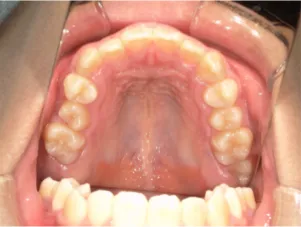

治療後⑤中3:咬合治療終了 マルチブラケット法の期間は9か月

| 行ったご提案・診断内容 | 成長期に行う治療と咬合治療をご提案しました。 成長期治療(成長時期にお口の環境を整え、適正な成長を促す治療)で、 ①歯列弓形態の修正、拡大と前歯を並べる。 ②出っ歯を治す専用の装置を使用する。 ③・MFT:舌や口唇などが正しい動きやポジショニングで機能し、鼻で呼吸できるようにする練習、毎日おうちで習慣づくように続けてもらいます。 ④拡大による顎顔面の適正な成長効果で口元を改善する(写真③)。 |

| 治療のリスクについて | 凸凹(でこぼこ)や口元の突出が残る場合は、抜歯治療へ移行します。 その他、矯正治療に伴うリスクとして、歯ブラシ不足による虫歯・歯周病、装置による違和感・痛み、口内炎、話しにくい・食べにくい、歯肉退縮、歯髄壊死、歯根吸収、顎関節症の悪化などがあります。 |